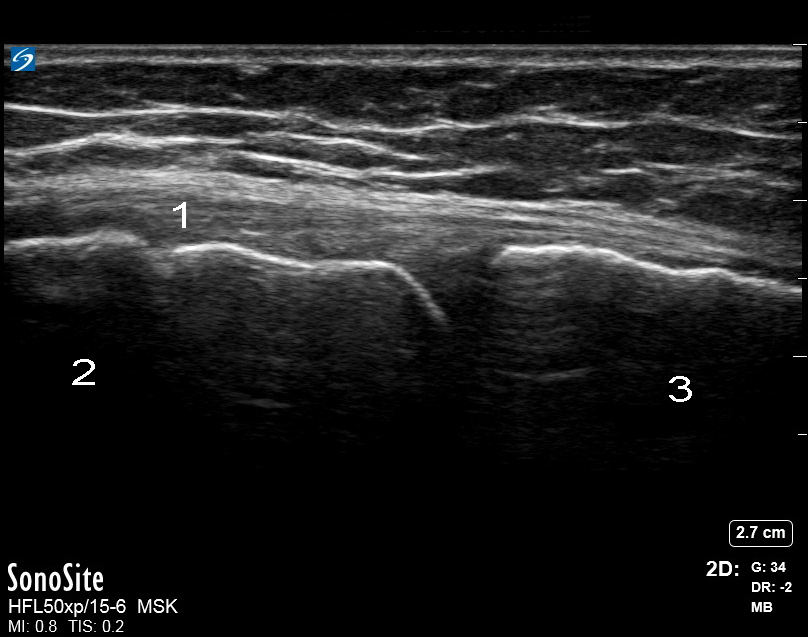

膝部:内侧副韧带 (MCL) 图像

内侧关节线

内侧副韧带 (MCL)

股骨

胫骨